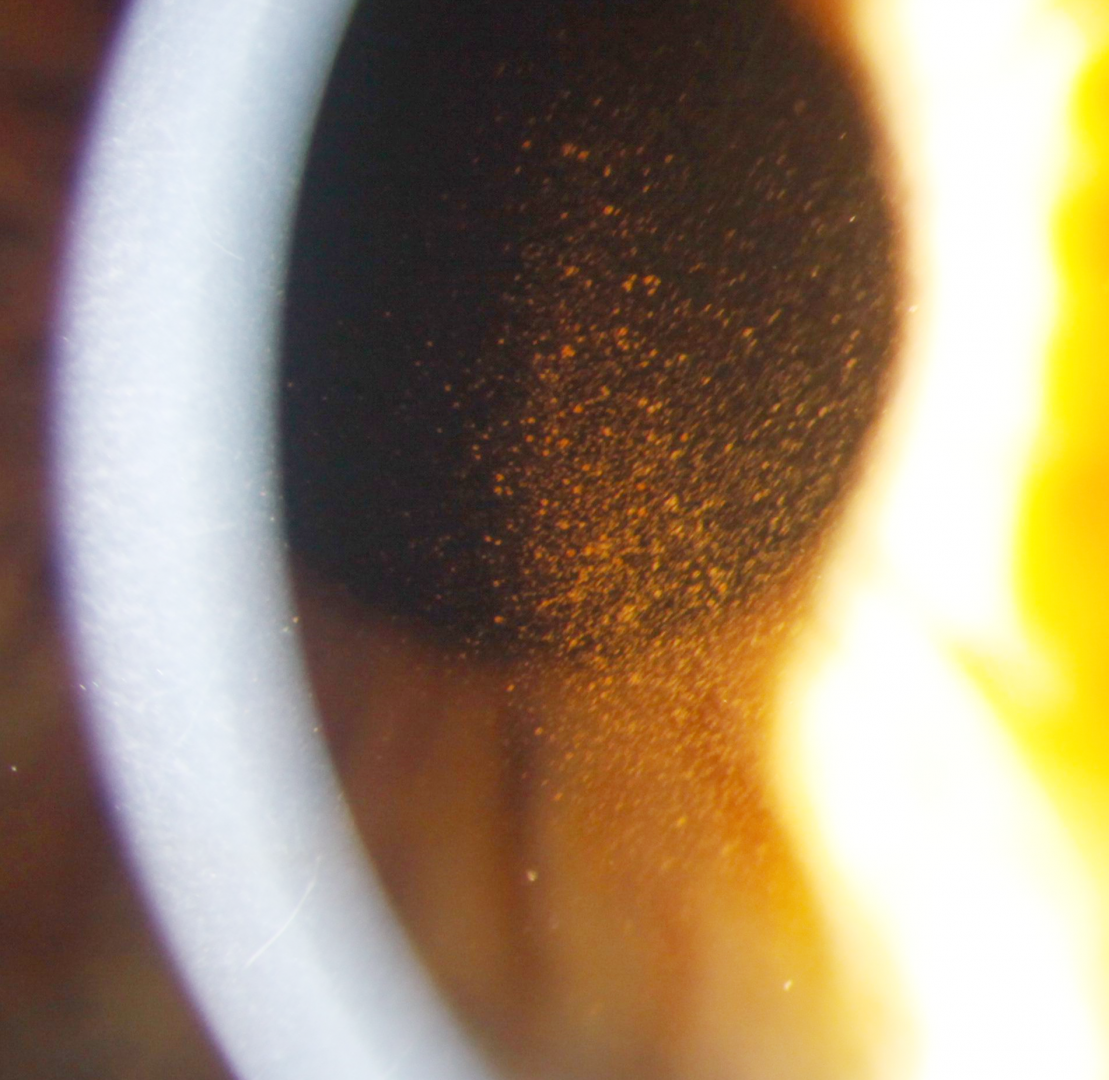

Pigment dispersion syndrome is typically characterised by the presence of 3 key clinical signs - pigmented cells deposited vertically on the corneal endothelium (1-Krukenberg's spindle), mid-peripheral iris transillumination defects (2) and increased, uniform pigmentation of the trabecular meshwork on gonioscopy (3). The pigment deposited in the trabecular meshwork is typically uniform in distribution, in contrast to the patchy pigment deposition seen in pseudoexfoliation syndrome.

Case 1: Active pigment dispersion syndrome

A 30 year old male with intraocular pressures of 27mmHg in each eye in the context of thick corneas (central corneal thickness 590µm OD, 605 OS).